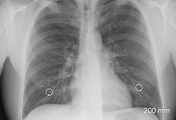

| 호흡곤란 기흉 증상 및 원인과 치료법? (0) | 2020.04.08 |